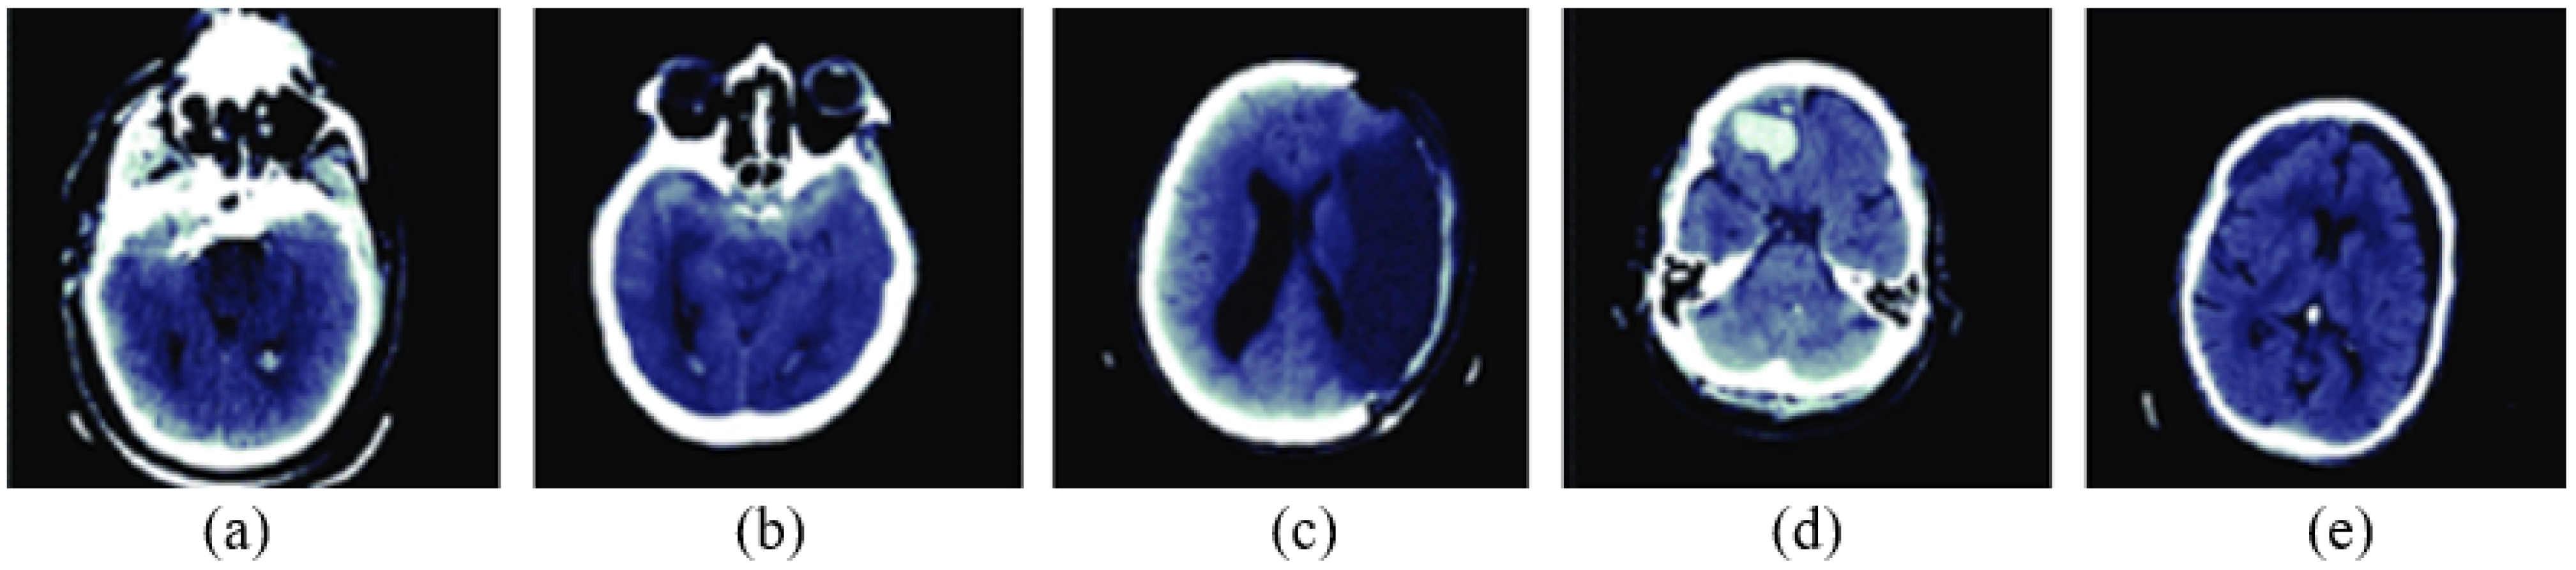

3.2. Image Segmentation